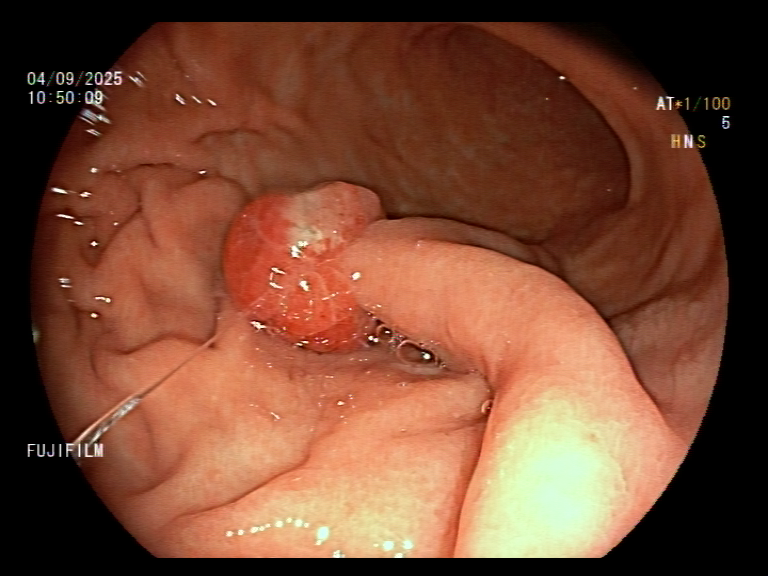

1. Antrum, low grade dysplasia. Removed via ESD. Specimen 43x32mm / dysplasia 20x13mm. R0